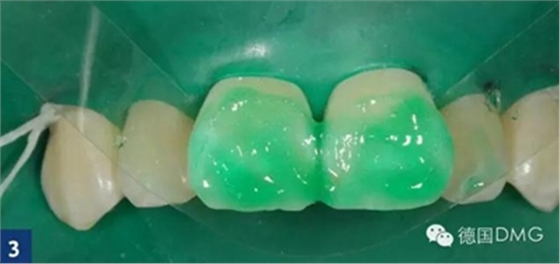

應(yīng)用icon酸蝕劑酸蝕唇面2分鐘(Fig. 3).

由于最初的酸蝕結(jié)果并不令人滿意,因此我們重復(fù)酸蝕步驟. 利用乙醇干燥之后,可以看到顏色的改變。但是酸蝕結(jié)果還是不滿意,因此我們進(jìn)行了第三次酸蝕。在每一次酸蝕之后, 都應(yīng)將酸蝕劑徹底沖洗干凈然后用icon干燥劑進(jìn)行干燥 (Fig. 4).